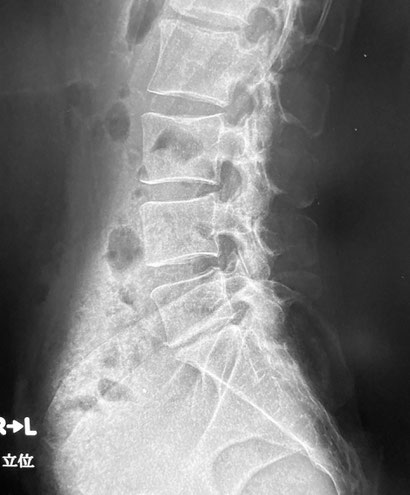

椎間板腔狭小化の解説(L5-S1)

MRI検査が最も詳細な評価を可能にしますが、実際の臨床現場では、まずレントゲン検査が行われ、その際に「骨の間が狭くなっている」と説明されることが多くあります。

その所見の意味について解説します。

レントゲンで見える「椎体(骨)の間が狭い」とは

レントゲンで「骨と骨の間が狭い」と言われるのは、背骨と背骨の間にある椎間板(クッションの役割をする軟骨組織)が、少しずつ薄くなっていることを意味します。

椎間板は、年齢や日常生活での負担によって水分が減り、弾力を失っていくため、徐々に薄くなることがあります。その結果、レントゲンでは骨と骨のすき間が狭く見えるようになります。

この「骨の間が狭い」という所見は、椎間板の変性やすり減りが進んでいる可能性を示しています。必ずしも強い痛みが出るとは限りませんが、腰痛や神経の圧迫によるしびれの原因になることがあります。

特にL5-S1(腰椎の一番下の部分)は、体重や動作の負担が最もかかりやすいため、加齢や使いすぎで変化が起こりやすく、レントゲンで椎間板の隙間(椎間板腔)が狭く見られることがあります。